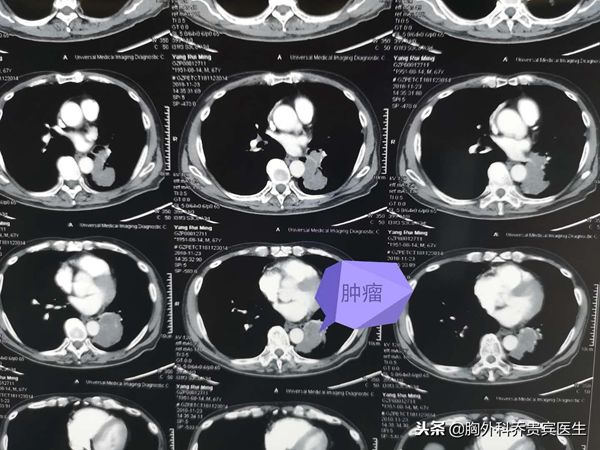

老人近期因为咳嗽,痰中带血去医院检查,结果发现左下肺有一个巨大肿块,肿块已经侵犯气管和血管。经过病理活检,确诊是一个大细胞肺癌。

二、尝试手术切除肿物,缓解病人的症状,术后生存期在二年左右或是长期。手术的前提条件是,由于肿物太大,而且有侵犯,需要先进行化疗,如果能明显缩小,才有手术机会,但是术后还需要进行化疗治疗。

近日,用了三个小时给老人完成了这个艰难的手术,胸腔镜下左下肺切除,支气管成形,因为化疗后粘连,术中渗血比较多,又要做腔镜下的吻合。术中也差点因为情况严重而中止手术,最后还是在坚持和努力下完成了。术后老人再配合相应的化疗,希望能达到预期的效果。